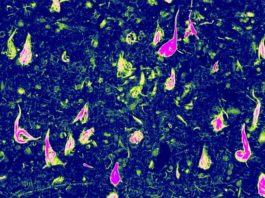

La sobreexpresión del gen Nrf2 en los astrocitos ralentiza el Alzheimer...

El aumento de la expresión de un gen en las células que ayudan a las neuronas del cerebro las protege en modelos de ratones...